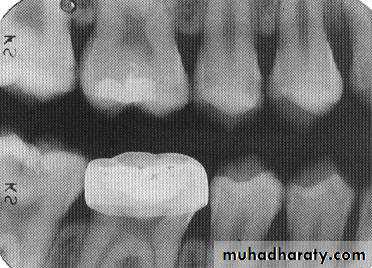

Dental materials. This radiograph shows several metallic and non-metallic dental materials. Since all of the metal restorations are equally radiopaque, their size and shape is observed to determine the type of material. The materials present in this radiograph are: (1) amalgam;(2) porcelain-fused-to-metal crown; (3) post and core; (4) gutta percha; (5) base material; (6) full metal crown, which is the posterior abutment of a three-unit bridge; (7) retention pin; and (8) metal pontic (part of the three-unit bridge).

Restorative Materials

Retention pins. (1) Radiopaque pins help retain the radiolucent composite restorations. (2) Small radiopaque amalgam restorations.